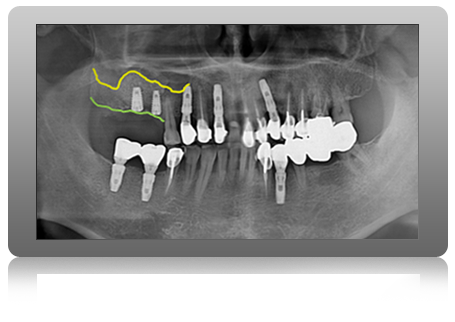

REIMPLANT CASE

CURE PART IMPLANT - 임플란트 재수술

REOPERATION IMPLANT

재수술 임플란트

잘못된 임플란트 수술로 고통 받고 있다면, 다시 선택해야 됩니다.

정밀한 분석으로 근본적인 원인을 파악하여 실패한 임플란트를 다시 성공시키는 임플란트 재수술